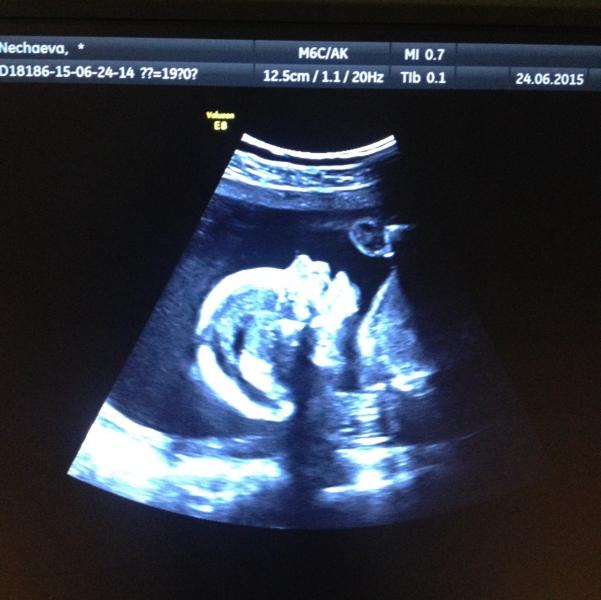

А у нас будет вторая доченька👯🙏 я очень рада ) муж растроился...ну ничего... Какие наши годы) 🙈

@mamsik, нет это плановый 19 недель) делала у костюничева в перенатальном

поздравляю! а где делали?не дождались второго скриннинга?